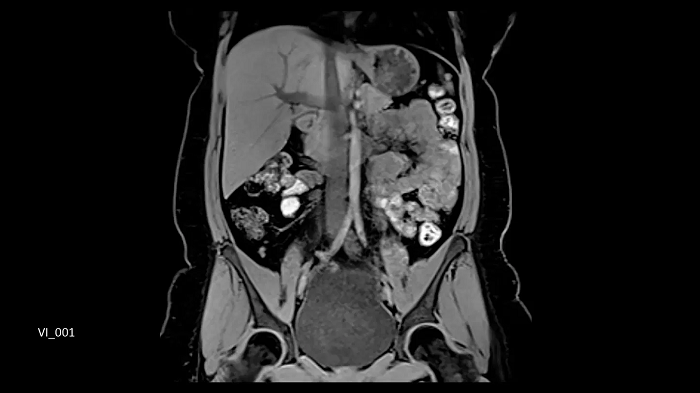

Whole-body imaging

Full Whole-Body Coverage in Only 5 Stations

Enhanced whole-body DWI quality due to BioMatrix SliceAdjust.

- BioMatrix Head/Neck 20

- BioMatrix Spine 72

- 2× Body 18

- Peripheral Angio 36

Image Credit: University Hospital Tubingen, Germany